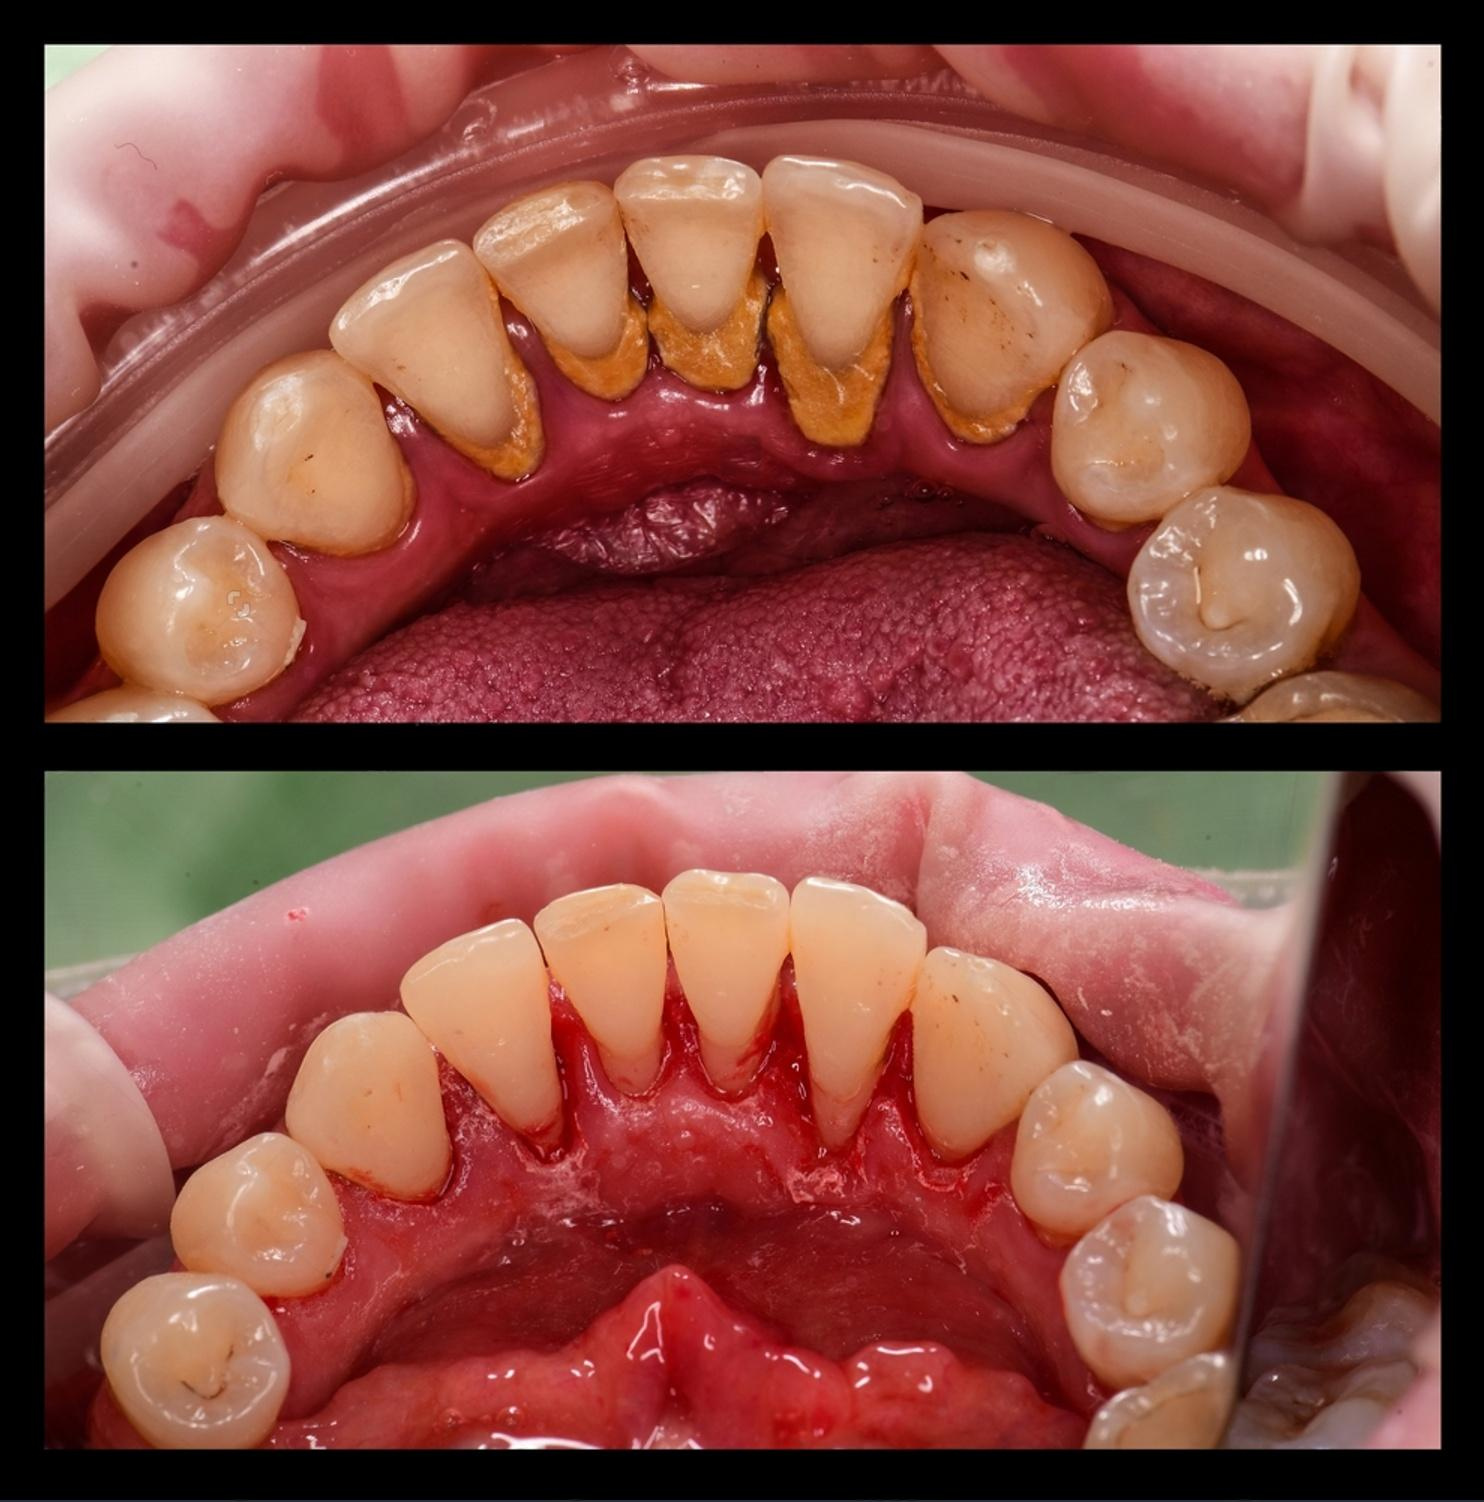

Real Results. Real Confidence.

At Al Rayashi Dental Center, we believe that every smile tells a story — and we’re proud to be part of so many incredible journeys. Our Smile Transformations page showcases real patients who have trusted us to restore their confidence and enhance their dental health.

From subtle refinements to dramatic changes, these before-and-after cases highlight the power of expert care and advanced dental technology.

Smile Transformations